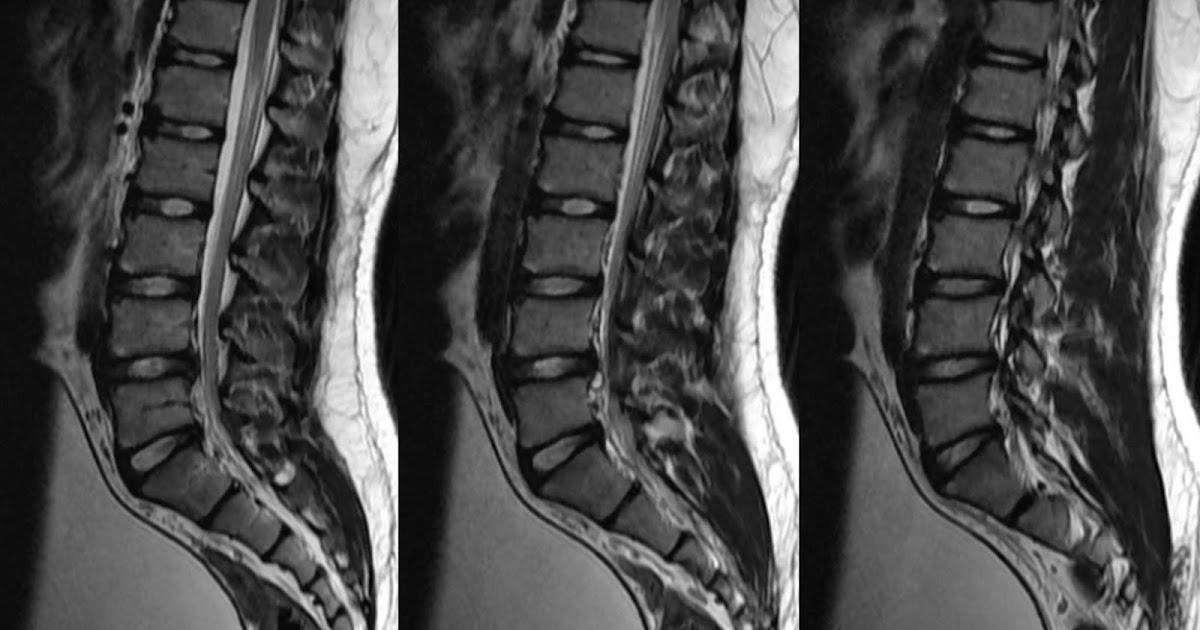

spine cyst june 2010 copy An Mri scan of my spine taken Ju… Flickr

spine cyst june 2010 copy An Mri scan of my spine taken Ju… Flickr Cyst Back Spine They may cause pain and lead to other spinal conditions. a synovial cyst is a relatively uncommon cause of spinal stenosis in the lumbar spine (lower back). It may cause pain, tingling, or. They form because of degeneration or injury (as a way to protect the injury). These cysts are not uncommon. It is a benign condition, and. . Cyst Back Spine.